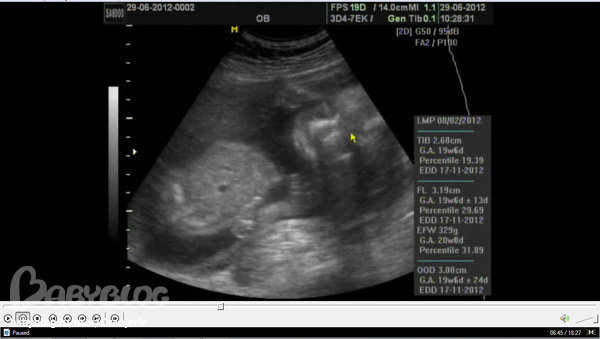

Вот наше чудо в 9 недель и 1 день, уже совсем человечек)))

Просто седцебиение есть уже в 5,5-6 недель. А порассматривать пальчики и ножки реальнее на первом плановом узи, которое делается на сроке 11 недель 1 день - 13 недель 6 дней.

далее - второе плановое в 20 недель и 2 дня (но в Москве, слышала, его делает с 16 по 18 неделю почему-то). Там уже совершенно взрослый человечек! И пол четко виден=) И черты лица...